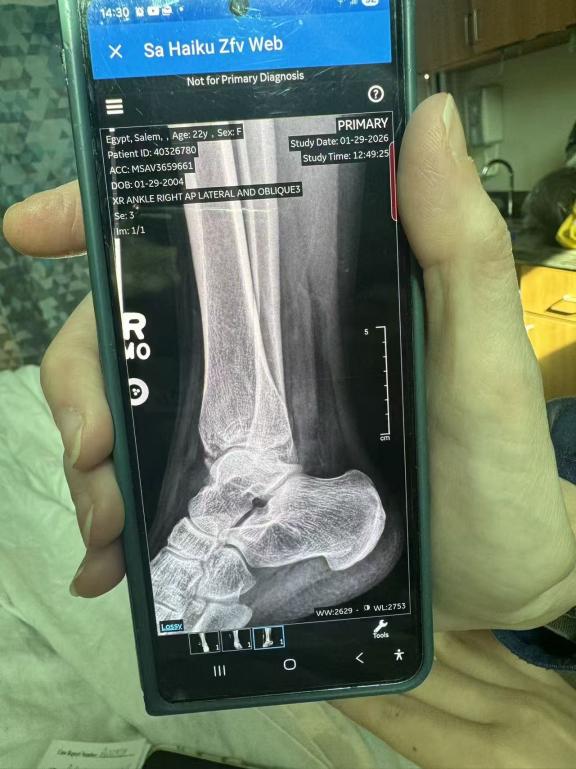

随后,救援团队第一时间与C女士取得联系,并迅速建立专属微信服务群,远程指导上传女儿的就诊记录、诊断报告和X光片。专业医护人员对伤情进行紧急评估,并持续指导后续就诊、复诊及休养安排。